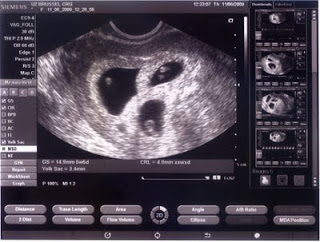

La première échographie nous a permis de voir trois beaux bébés en santé qui verront le jour quelque part en octobre.